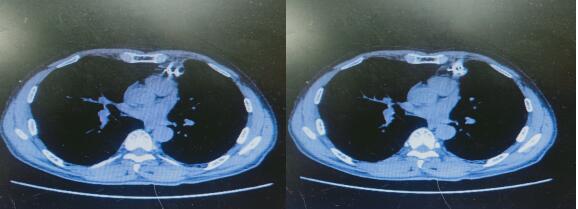

↑ 术前检查

患者陶某,2020年12月13日因胸痛来我院就诊,门诊给予胸部CT检查显示左肺上叶肿瘤并左肺内转移,之后住入血液内科,入院完善检查后行CT引导下肺肿瘤穿刺活检,术后病理示:左肺鳞癌,刘金峰主任根据患者情况给予综合评估,考虑患者胸痛明显,结合最新治疗指南后于2020年12月25日行左肺癌碘125粒子置入术,手术顺利,术后恢复好。术后10余天胸痛就明显好转。为进一步巩固治疗,之后再次给予全身化疗4周期。患者目前胸痛消失,胸部肿瘤较前体积明显缩小。